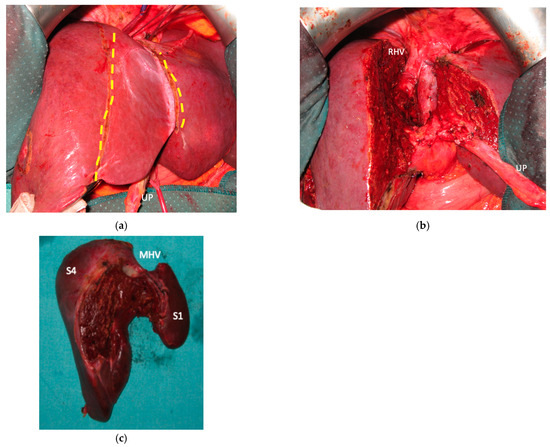

2.6. Staged e-ALPPS (Staged Enhanced ALPPS): Deportalized Liver Parenchyma-Sparing Resection as Intermediate Stage

This intervention is performed when FLR does not reach an adequate volume after the first stage of e-ALPPS. Vessel-guided dissection and vascular reconstructions are used to assure R0 resection for this intermediate stage. One week after FLR volume is re-evaluated for the third stage to remove deportalized liver and to complete R0 e-ALPPS. See Figure 2.

3.4. Staged (PS) e-ALPPS

In six patients the resection of first-order GP was planned and e-ALPPS was performed. Four e-ALPPS were parenchyma sparing since a part of S4 was preserved (in deportalized liver in one case of FLR = part of S6/S7, see Figure 9).

In four cases the Spiegel lobe was preserved. At the first stage (MLP) MHV was resected in four cases, preserved in deportalized liver in the case of FLR = part of S6/S7 and reconstructed with an end-to-lateral anastomosis with LHV (FLR = S4b/S2/Spiegel lobe) in one case. In two patients (FLR 15% = part of S4/S2 and Spiegel lobe; FLR 7% = part of S2/S3) FLR volume was deemed inadequate after the first step of e-ALPPS (FLR 29% and 28%, 15 and 17 days after the first stage), daily liver growth after the first stage was 21 mL/day in the first 8 days and 8 mL/day in the subsequent 7 days in one case and 19 mL/day in the first 17 days in the other (in the latter, growth kinetic cannot be evaluated during the first week since CT was not performed). Intermediate stage of partial resection of the deportalized liver was performed (in both cases resection of S5-S8, in one case en-bloc with RHV which was reconstructed with an end-to-end anastomosis). Seven days after the intermediate stage FLR volume increased up to 39% and 41% with a daily growth of 18 mL/day and 25 mL/day. The third stage to complete the ALPPS procedure was performed (23 and 27 days after the first stage) resecting the last part of deportalized liver (S6/S7). In both cases the left hemicolectomy was associated to third step of staged e-ALPPS (see Figure 10, Figure 11, Figure 12 and Figure 13).

In a case of e-ALPPS an intermediate stage of PSH of the deportalized liver was necessary (due to inadequate FLR volume of S2/S3 18 days after the first stage), at the intermediate stage S5/S8 were resected en-bloc with RHV which was reconstructed with an end-to-end anastomosis (Figure 11).